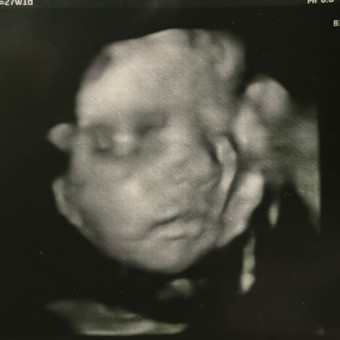

Baby Noah’s Registry

Kirsten Lawson

Zoe, KY

May 17, 2026